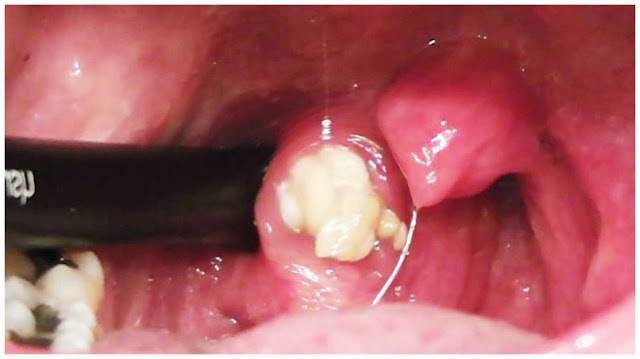

HERE’S WHY YOU HAVE ‘BAD BREATHE”. REMOVE THIS AND SOLVE THE PROBLEM!

Do you suffer from bad breath no matter how many air fresheners for that you have used? read more here > healthylifeidea.com